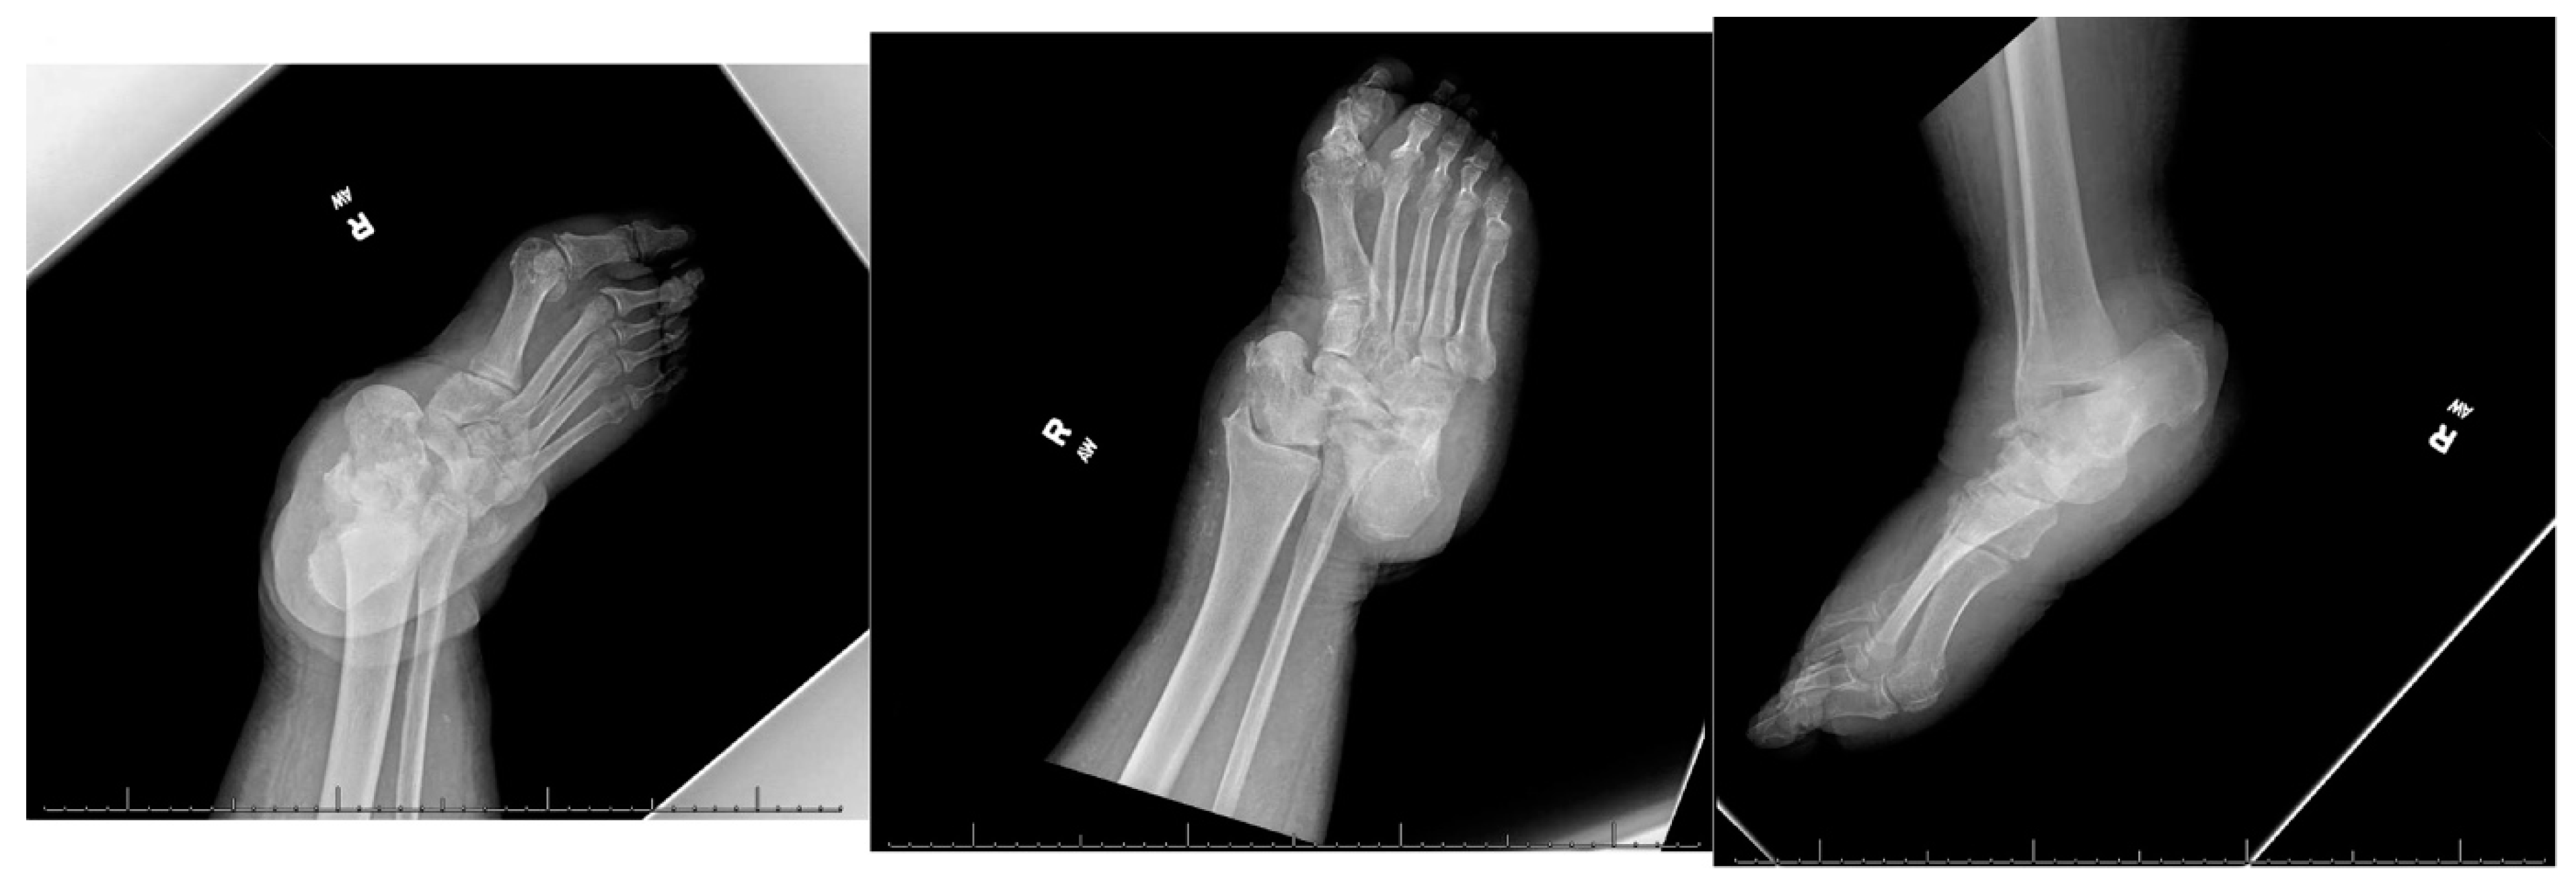

The surgical wound healed primarily, and the patient completed the six-week parenteral antibiotic course without any incidents. The patient remained afebrile, and the infection blood markers returned to normal range. At eight weeks, the second stage of surgical reconstruction was planned as an outpatient surgery. Given the patient’s comorbidities and less-than-desirable living conditions in a rural setting, internal fixation was preferred over external fixation. A retrograde hindfoot intramedullary nail was selected for internal fixation. The former medial skin incision was reopened, removing the cement beads. The joint surfaces of the tibia, calcaneus and the navicular bones were prepared using a combination of rongeurs, curettes, and drills to obtain raw surfaces. A separate lateral incision over the distal fibula was created, approaching the distal fibula. After meticulous subperiosteal dissection, a 3 cm distal fibula was resected and nibbled into cancellous bone chips. Next, the calcaneus was manually reduced, aligning the posterior tuberosity with the distal tibia and anterior process with the navicular bone. The calcaneus was fashioned minimally to facilitate adequate reduction using rongeur and rasp. Once the reduction was deemed acceptable by biplanar fluoroscopy, multiple Kirshner wires were inserted for provisional fixation. A 10 mm intramedullary hindfoot nail was inserted in a retrograde fashion using standard technique and stabilized with one calcaneal and two tibial locking screws. A headless compression screw was inserted in an antegrade fashion outside the internal nail to supplement the fixation of the tibio-calcaneal interface (Figure 7).

Figure 7. Intraoperative fluoroscopic images showing restoration of axial alignment with retrograde hindfoot nail and headless compression screw.